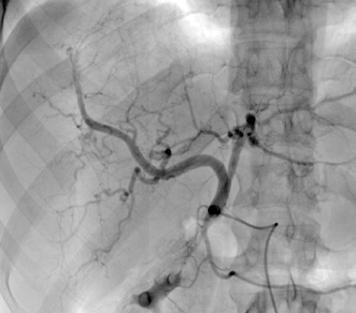

Angiografía previa a la embolización con micropartículas. A través de la femoral, accedemos a la aorta (Ao). De la aorta accedemos a la arteria mesentérica superior (AMS), de donde sale en este caso la arteria hepática (AH). Se divide en arteria hepática derecha (AHD) y arteria hepática izquierda (AHI). Se emboliza la AHD y una rama distal de la AHI. Vemos cómo ambas ramas dan abundantes ramas que irrigan la lesión.

la hepática derecha y una rama más distal de la hepática izquierda, preservándose los segmentos II y III. (Figura 3)